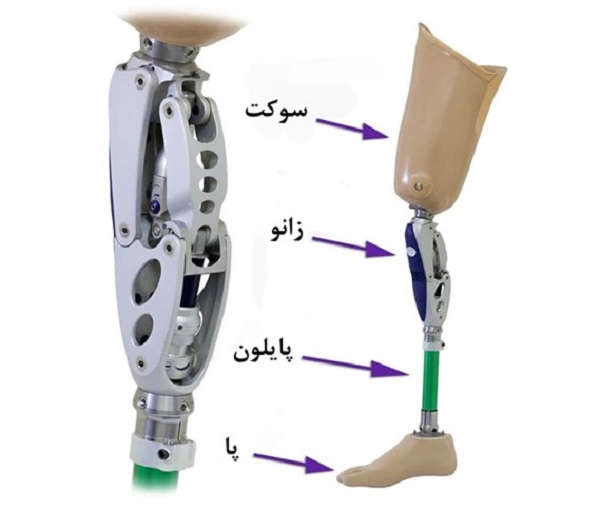

اجزای تشکیلدهنده پروتز پای مصنوعی

پروتز پای مصنوعی از اجزای مختلفی تشکیل شده است؛ این اجزا با هم کار کرده تا تحرک و عملکرد پا را شبیهسازی کنند. در اینجا بخشهای مختلفی که معمولاً در پروتز پا یافت میشود را میتوانید مشاهده کنید:

- سوکت (Socket): سوکت بخشی از پروتز است که استامپ یا اندام باقیمانده درون آن قرار میگیرد. این سوکتها به صورت سفارشی طراحی و ساخته میشوند.

- مفصل زانوی مصنوعی: در پروتزهای قطع عضو بالای زانو، یک مفصل مصنوعی زانو وجود دارد تا خم شدن و امتداد ساق پا در حین راهرفتن فراهم شود.

- پایلون (Pylon): پایلون به بخش اصلی داخلی پروتز گفته میشود که سوکت را به استامپ متصل میکند. این بخش ثبات و انتقال نیرو را در حین راه رفتن فراهم میکند.

- پنجه و مچ پای مصنوعی: این بخش وظیفه جذب ضربه و پشتیبانی از فعالیتهای مختلف در پروتز پا را دارد.